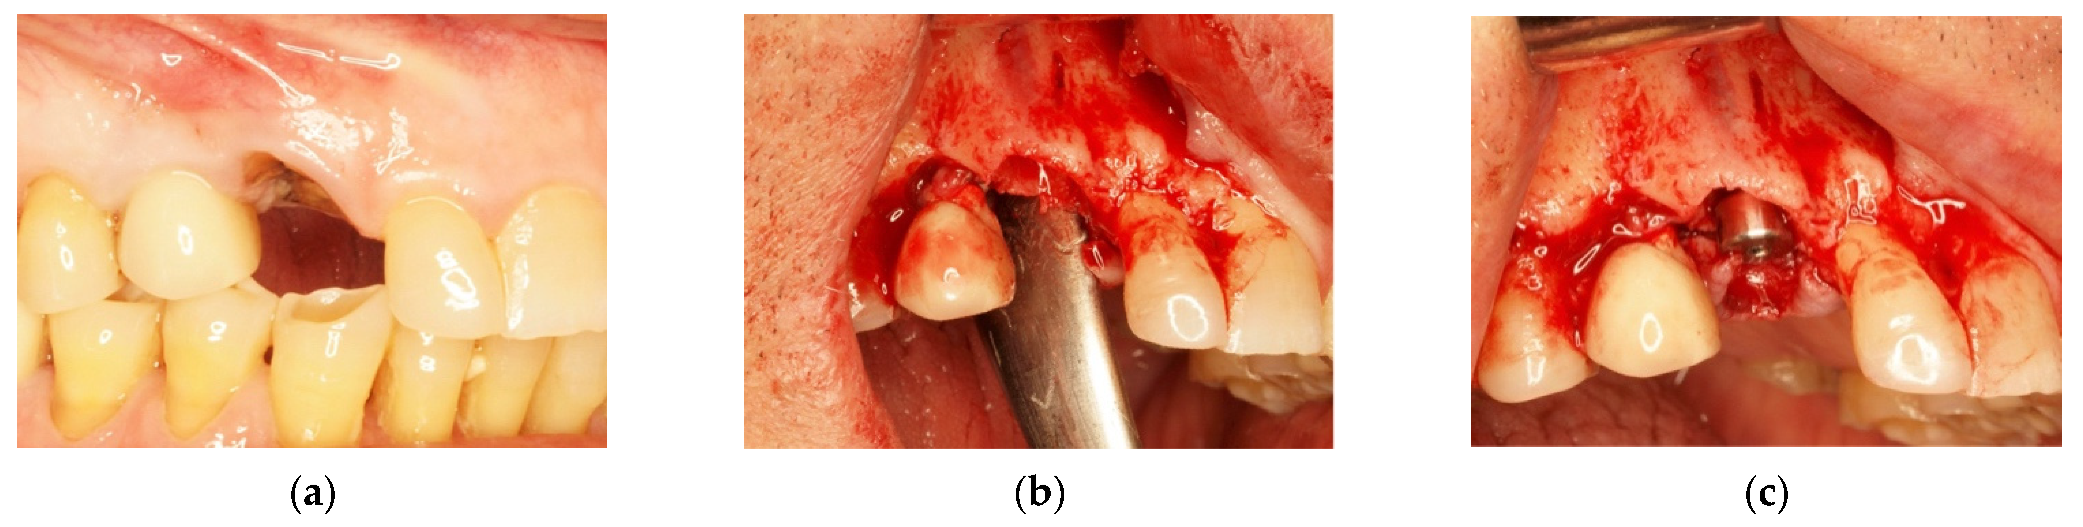

4.1. Clinical Case n.1.

4.2. Clinical Case n.2.

4.3. Clinical Case n.3.

4.4. Clinical Case n.4.

4.5. Clinical Case n.5.